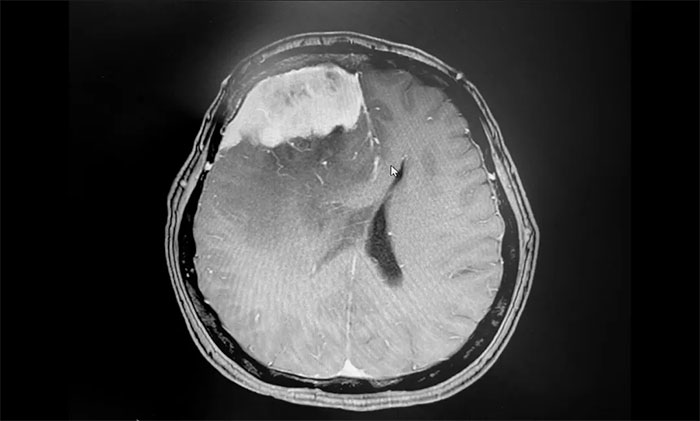

▲ 术后影像,肿瘤已切除

手术顺利完成后,患者生命体征平稳,安返监护病房。留取病理标本送检,确定为脑膜上皮型脑膜瘤(WHO I级),为良性肿瘤。